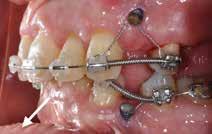

PATIENTTILFÆLDE 1

Patienttilfælde 1 (Fig. 1) er en 37-årig kvinde, henvist efter succesfuld behandling af stadie 3-parodontitis. Der er nu sundt

Før behandling

parodontium, ingen pocher over 4 mm, og både blødnings- og plakindeks er under 10 %. Patienten er motiveret for ortodontisk behandling, da hendes tænder er vandret over tid, delvist som følge af reduceret parodontium.

Der ses anterior trangstilling i begge kæber og overerupterede 1+1 og 2,1-1,2, hvilket resulterer i dybt bid med 2- tæt på ganepåbidning. Der er normale sidetandsrelationer, men der ses 5 mm horisontalt overbid (HOB) og 7 mm vertikalt

overbid (VOB). Papillen mellem 1+1 er betydeligt reduceret pga. fæstetab, og de mesialt kippede 1+1 har resulteret i en ”dark triangle”. Den facioorale funktion er for nuværende i.a. Panoramarøntgen (Fig. 1, I) viser marginalt knogletab i begge kæber og fravær af 8,7+7,8 og 8,7-8.

Objektivt anbefales behandling af det dybe bid, som ubehandlet forventes at forværres yderligere over tid. Patienten har ønske om behandling med æstetisk ortodontisk apparatur, alignere, og det vurderes muligt at behandle malokklusionen med alignere. Dog anbefales det generelt, at alignere undgås eller benyttes med væsentlige modifikationer af alignerens retention ved tandmobilitet, da dette ellers kan medføre jiggling, når aligneren tages af og på mange gange dagligt. På den anden side er der nogen evidens for, at alignerbehandling er associeret med bedre renhold og parodontal sundhed sammenlignet med fast apparatur (16).

Der planlægges alignerbehandling af begge kæber med intrusion af 1+1 og 2,1-1,2, nivellering af trangstilling UK med interproksimal reduktion (IPR) (Fig. 2 A, B) og senere IPR OK for reduktion af dark triangles mellem incisiverne efter nivellering. Patienten instrueres i at benytte alignere 20-22 timer/ dag med alignerskift hver 7. dag, og patienten ses hver 3.-8. uge under forløbet. Den første alignerserie består af 16 alignere for nivellering OK/UK og IPR i UK (Fig. 2). Efter denne serie planlægges IPR mellem incisiverne i OK for reduktion af dark triangles (Fig. 3) samt yderligere intrusion af OK og UK-fronten i 12 refinement-alignere. Patienten udviser god kooperation og er meget tilfreds med alignerapparaturet, som er mindre synligt end det faste apparatur (Fig. 4).